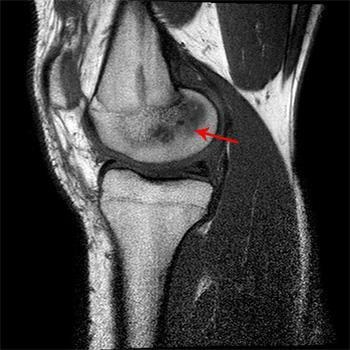

El edema óseo es una acumulación de líquido en el interior del hueso, generalmente en la médula ósea. Suele detectarse mediante resonancia magnética y está asociado a procesos inflamatorios o sobrecargas.

En la rodilla, puede afectar a estructuras como el fémur, la tibia o la rótula.